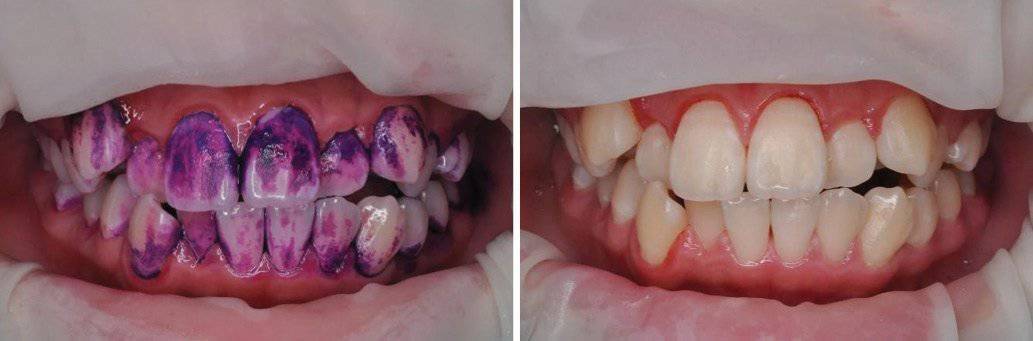

저희 치과에 방문해주는 소아부터 청소년 친구들 중에 가끔 양치를 잘 하려고 노력하지만 잘 안되거나 혹은 잘 안 닦이고 있는 사실을 모르고 있는 친구들이 있습니다. 소아청소년기에는 치아가 아직 경화가 덜 되어서 충치에 매우 취약할 수 있습니다. 단단하게 붙은 치태와 치석을 GBT를 통해서 치료해서 환자들에게 현상태 파악과 양치질의 중요성을 전달해줄 수 있으며, 무엇보다 충치를 예방해줄 수 있다는 사실은 매우 강점으로보입니다.(그림 3). 또한 성인 환자분들 중에서 흡연과 커피 소비에 의한 착색은 쉽게 지워지지가 않습니다. 이런 환자분들께는 특히나 환한 인상을 줄 수 있는 GBT를 적극 권해드립니다(그림 4).

[그림 3] : 청소년기의 환자로 GBT를 통해서 치태를 완벽히 제거하여 충치 예방을 시행

[그림 4] : GBT를 통해 심한 착색도 완벽히 제거가 가능합니다.